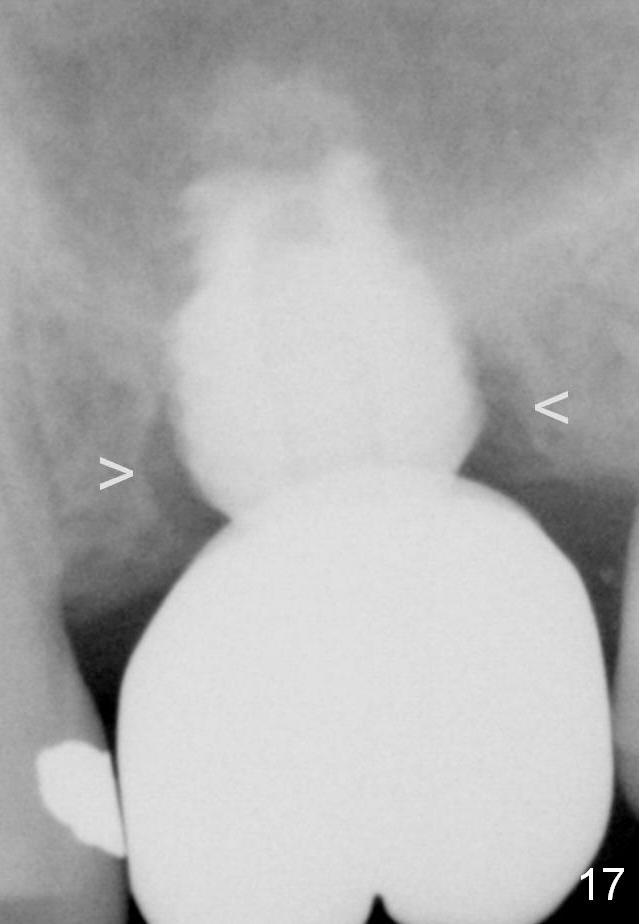

Although oral hygiene is pristine, there is apparent crestal bone resorption 12 months (Fig.16) and 20 months (Fig.17) post cementation, probably due to unfavorable crown/implant ratio and bruxism as well as pre-implantation bone loss (Fig.18,19).